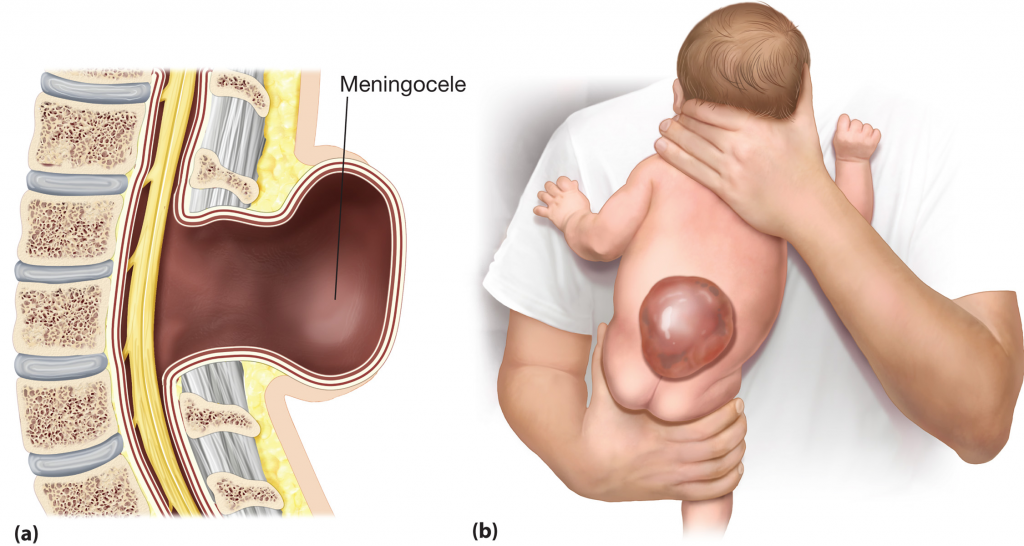

Рентген шейных позвонков при спина бифида

Раздел: Фотозарисовки